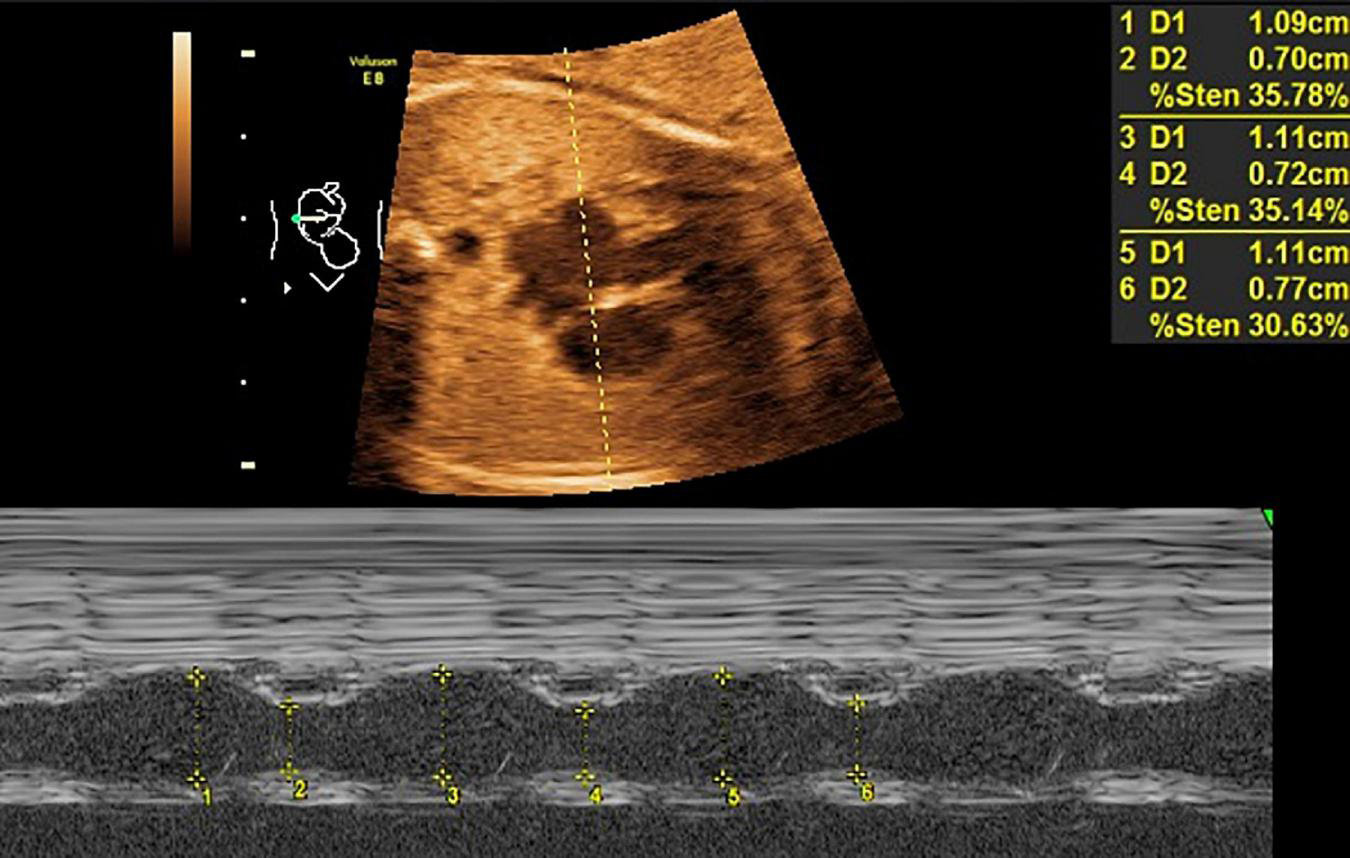

Mitral valve E/A ratio and tricuspid valve E/A ratio were not significantly different between the two groups (P > 0.05). GDM group showed significantly thicker IVSd (P < 0.001), higher DV-PI (P < 0.05), and significantly lower LASF than those in the control group (P < 0.001) (Figures 1, 2 and Table 2).

FIGURE 1

LASF in GDM fetuses at gestational age 26 weeks + 3 days. LASF, left atrial shortening fraction; GDM, gestational diabetes mellitus.

All women with gestational age of 24th–28th weeks underwent echocardiography. According to the echocardiography guidelines of American Society of Echocardiography (ASE) (9), pregnant women were placed in the supine position, and blood flow velocity of atrioventricular valve in early diastole (E peak) and late diastole (A peak) was measured to calculate E/A ratio. The blood flow spectrum in the ductus venous was acquired at the entrance of DV on the coronal section of the epigastrium. Ductus venosus pulsatility index (DV-PI) value was automatically recorded with a high-quality DV spectrum image acquired continuously within 3–5 cardiac cycles. IVS thickness at end-diastolic (IVSd) was recorded with M-mode in the long axis view. Then, the M-mode sampling line was moved to the left atrium, kept away from oval foremen, and the left atrial diameter at end-systolic (LAIDs) and end-diastolic (LAIDd) were measured successively, followed by LASF = (LAIDs-LAIDd)/LAIDs. All parameters were measured three times and averaged.